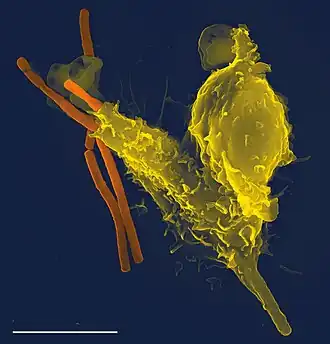

- Microbiology